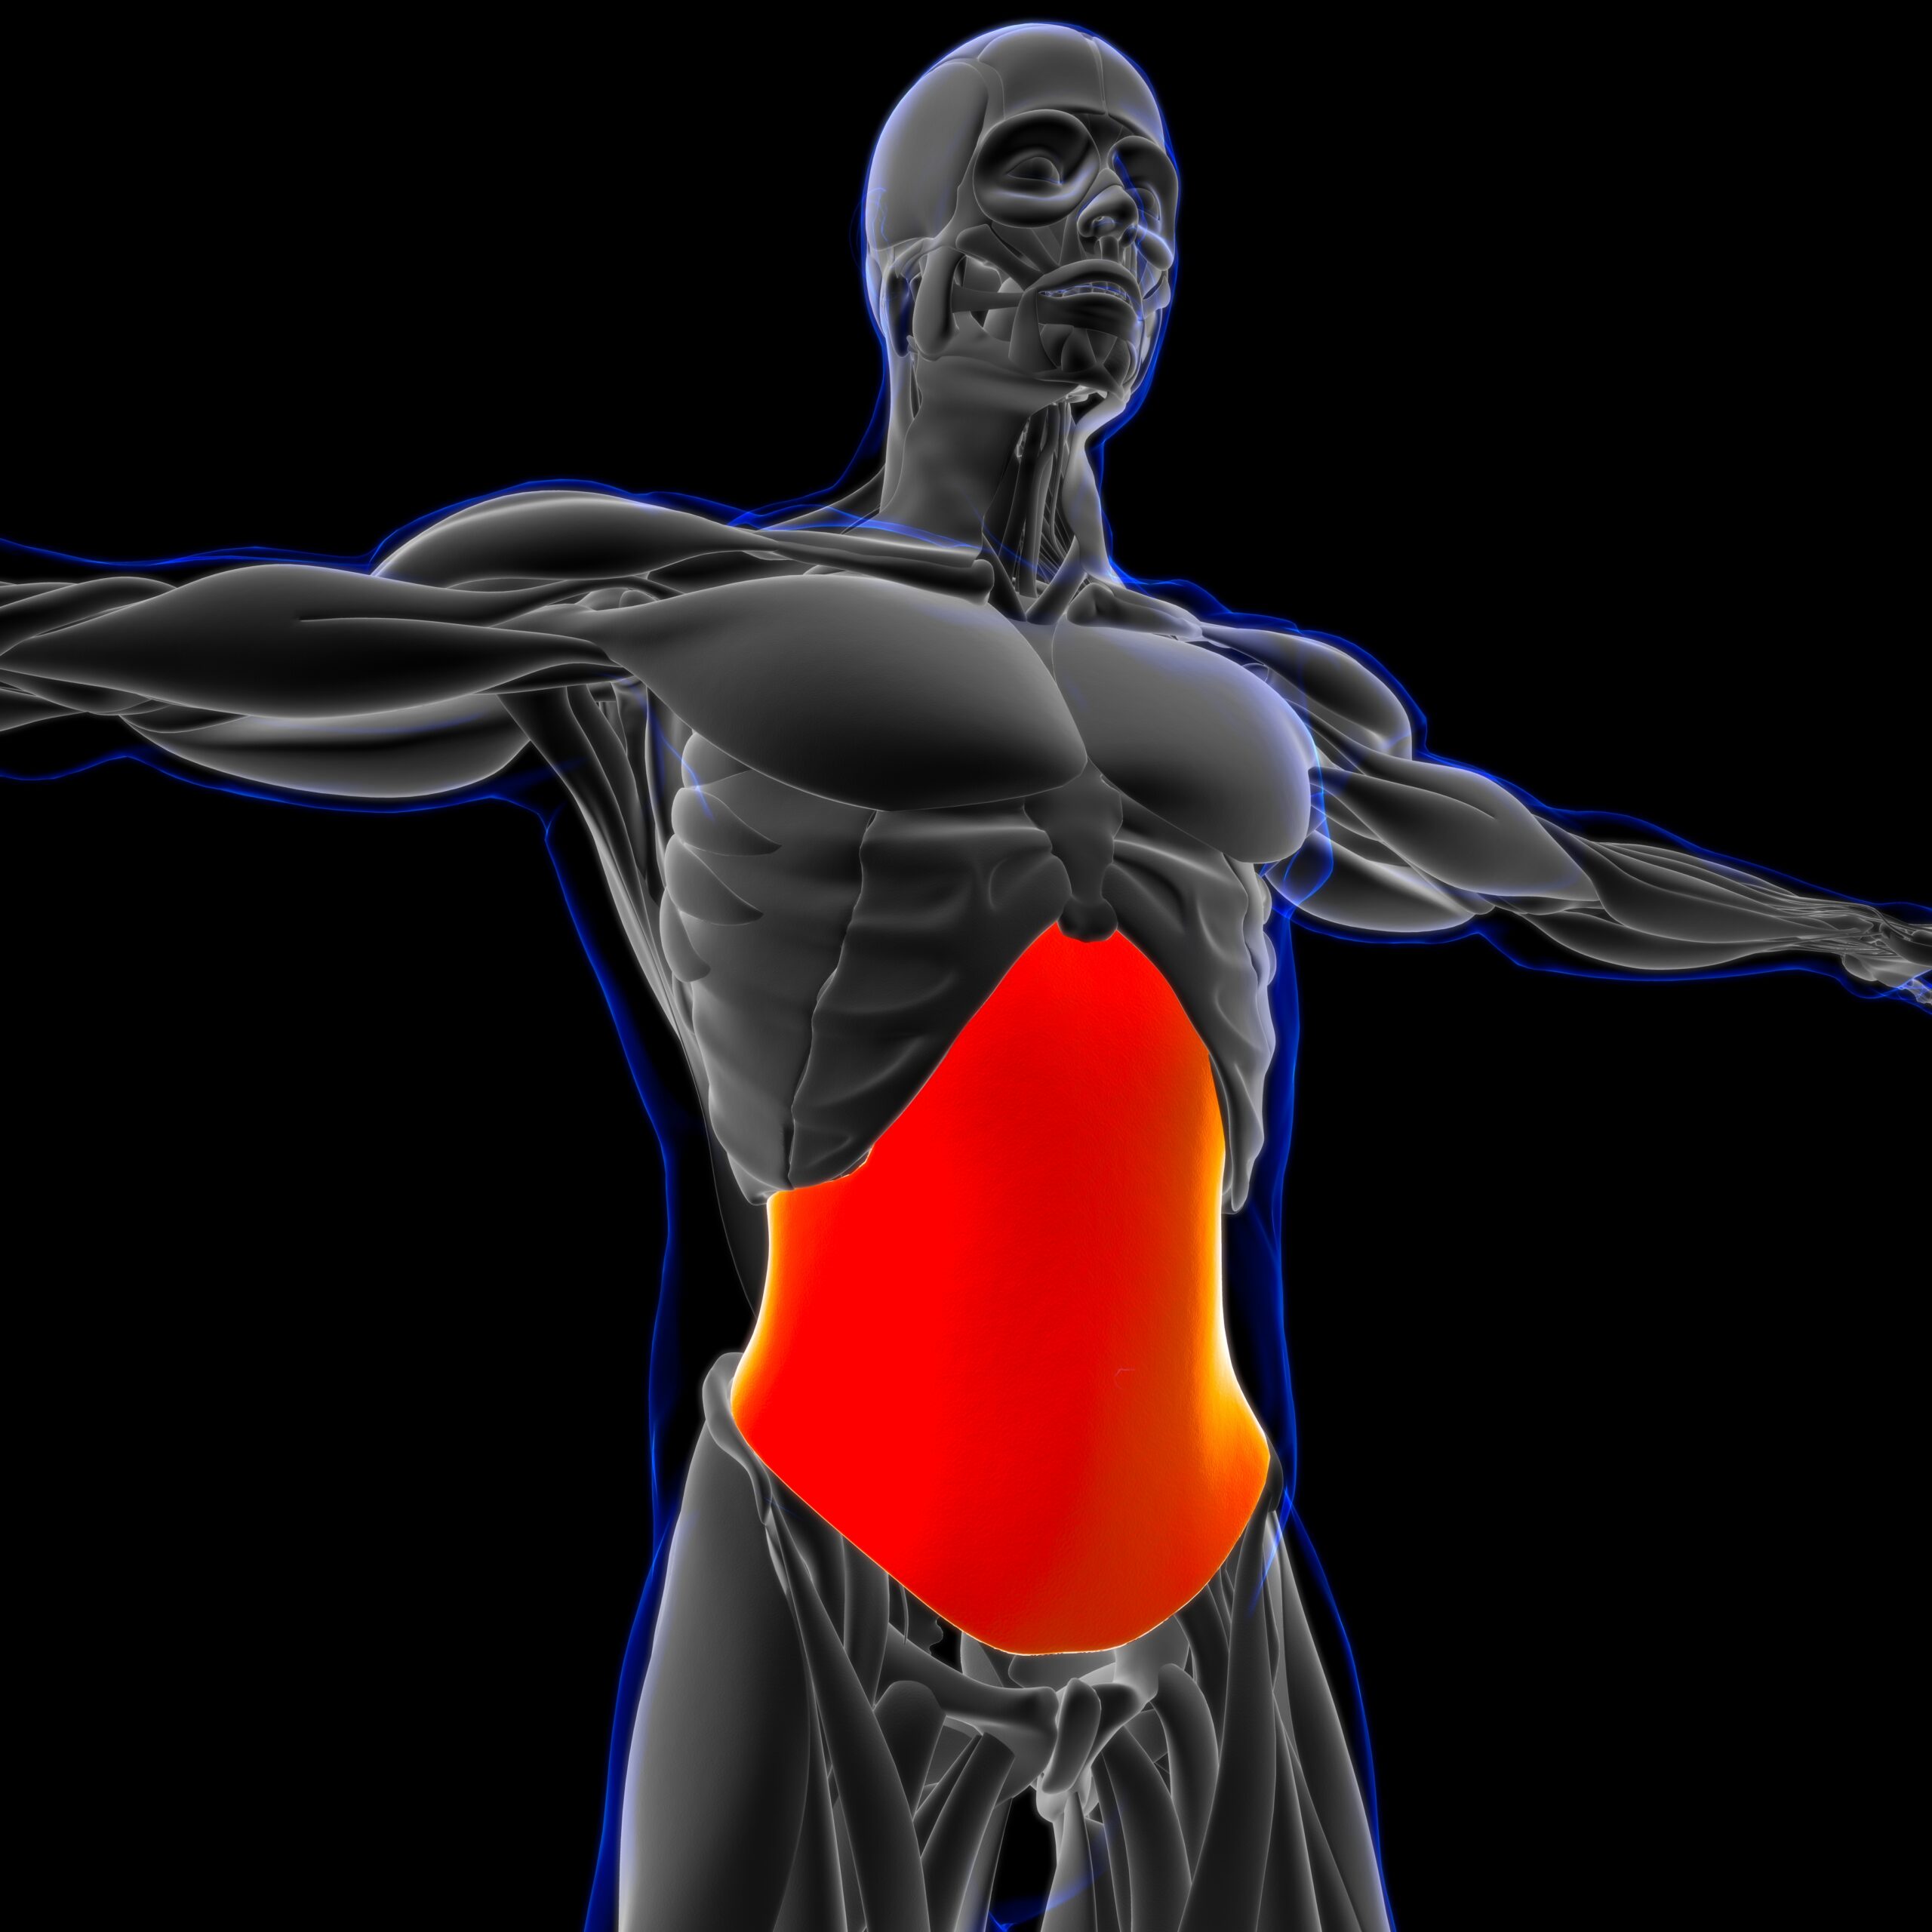

The inner abs muscle:

transverse abdominis

The body’s built- in corset. By toning it, the belly will be flatter and the waist slimmer, even without an extra diet. It doesn’t matter how much fat you have. If this muscle is strong, it will pull your waist together, as a result, making your belly look more compact, fit and toned. This is usually the first sign that people see after starting hypopressives.